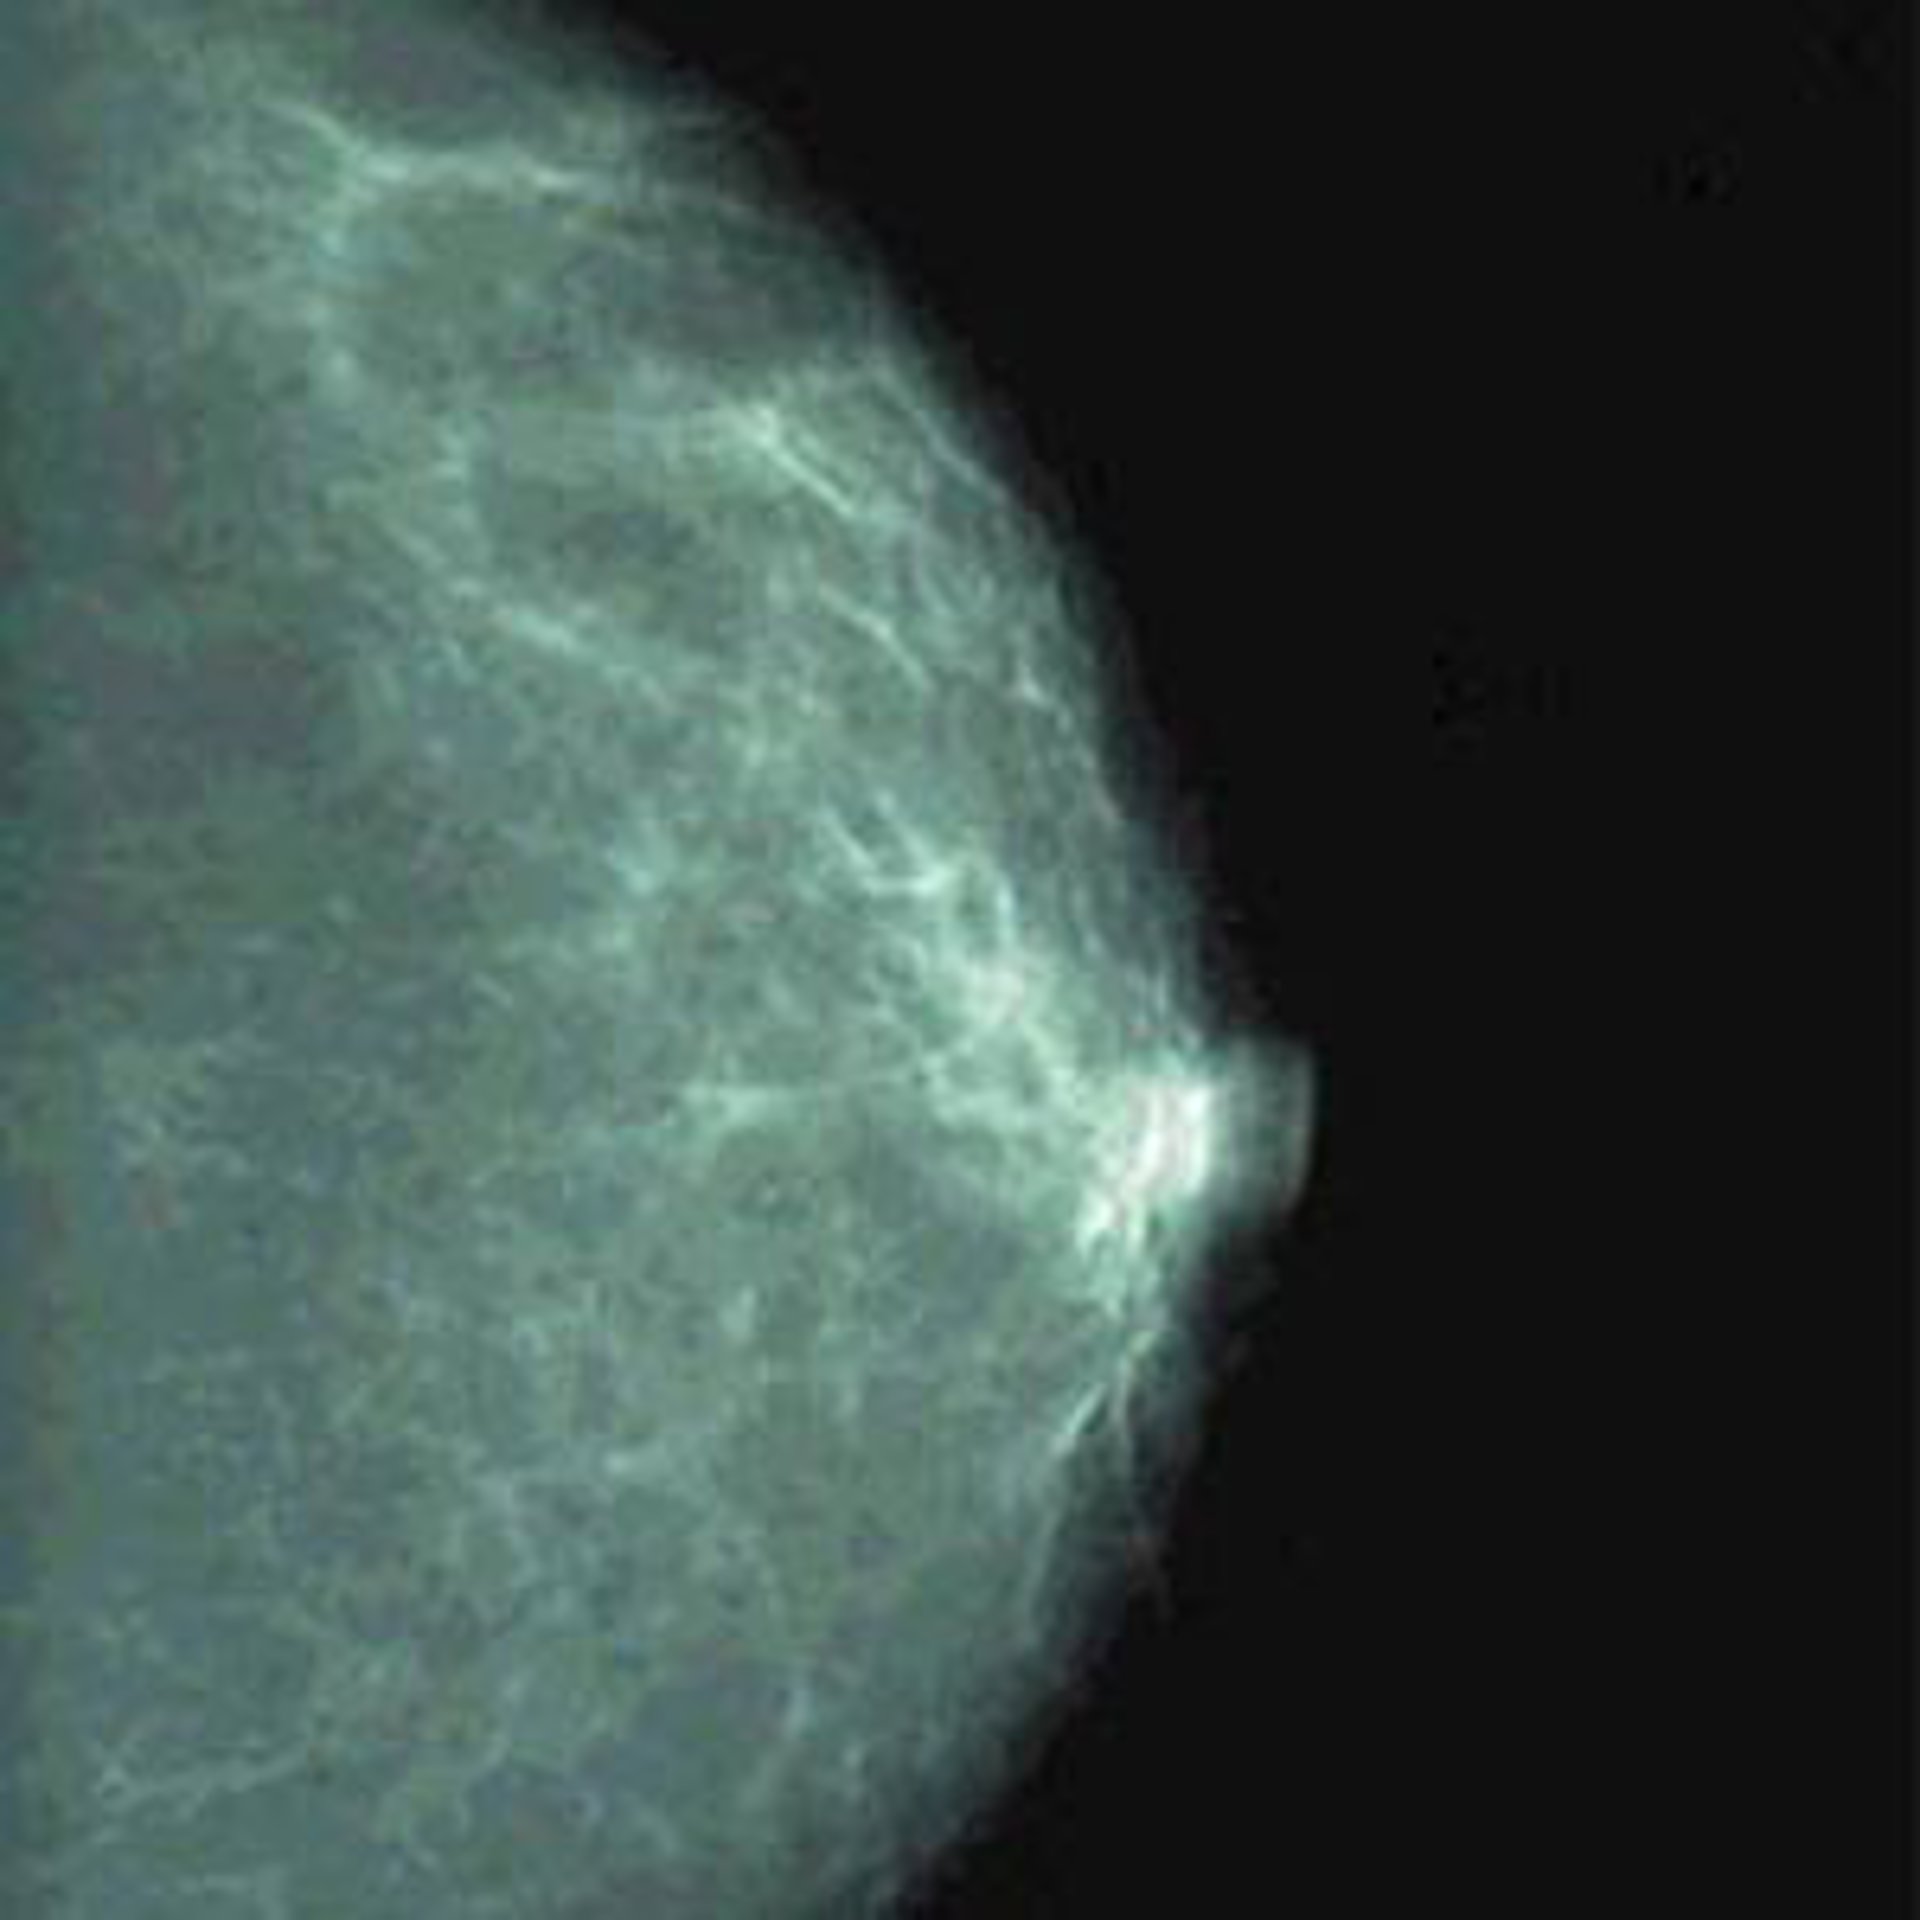

Expertos oncólogos se mostraron hoy partidarios de adelantar la edad de los programas de detección precoz del cáncer de mama mediante mamografía a los 40 años, durante la presentación del libro 'Cáncer de mama; Avances en diagnóstico, tratamiento e investigación', editado por la Fundación de Estudios Mastológicos (FEMA).

El doctor Armando Tejerina, director del Centro de la Mama de Madrid y presidente de la Fundación Tejerina, señaló que en el caso de pacientes asintomáticas sin ningún elemento de riesgo, las mamografías se deberían realizar sistemáticamente a partir de los 40 años. En el caso de pacientes asintomáticas pero con elementos de riesgo personales o familiares, o que quieran quedarse embarazadas, convendría hacer alguna mamografía a partir de los 35 años.

Por su parte, el doctor Juan Manuel San Román, jefe del Servicio de Cirugía de Mama y Cuello de la Fundación Jiménez Díaz, se mostró partidario de que los estudios preventivos comiencen alrededor de los 40 años y se prolonguen "hasta los 95", ya que el riesgo no disminuye con la edad.